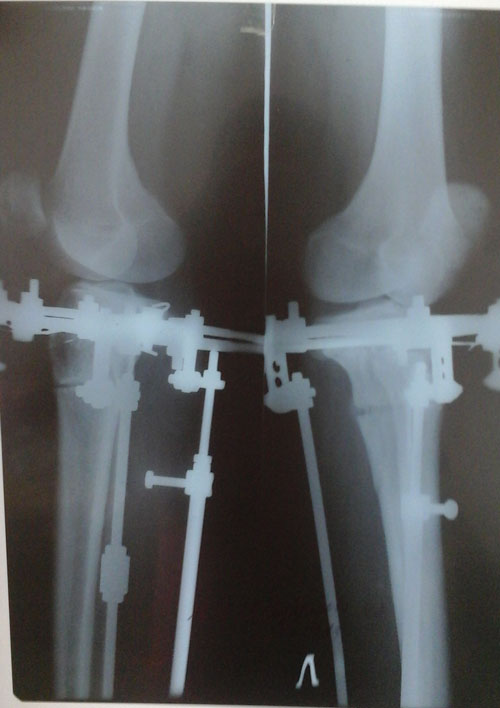

Рентген в 90 дней.

Здравствуйте, Марина! Сращение слабое, ждём рентген в 4 месяца.

IMG-20150916-WA0001-(1).jpg

20150916_154940.jpg